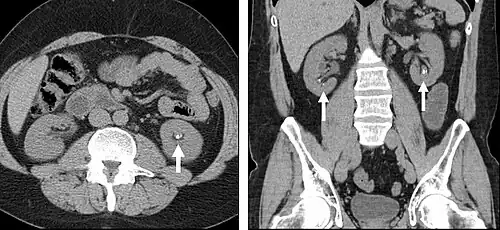

Detection and characterization of renal parenchymal masses is a frequent indication for CT. An initial noncontrast CT is important for detecting calcium or fat in a lesion, and to provide baseline attenuation of any renal masses. Following noncontrast scanning, intravenous contrast is injected and a corticomedullary phase is obtained at approximately 70 seconds (figure 7a, 7b). The corticomedullary phase is characterized by enhancement of the renal cortex as well as the renal vasculature. This phase is valuable in the evaluation of benign renal variants, lymphadenopathy and vasculature, however certain medullary renal masses may not be visible during this phase due to minimal enhancement of the medulla and collecting system. The parenchymal phase is obtained approximately 100–200 seconds after the injection of contrast material (figure 7c). Parenchymal phase imaging demonstrates continued enhancement of the cortex, enhancement of the medulla, and various levels of contrast material in the collecting system. The parenchymal phase is highly important for the detection and characterization of renal masses, parenchymal abnormalities, and the renal collecting system. This method of imaging does not evaluate for abnormalities of the collecting system.

-

FIGURE 7. Selected images from a renal mass specific protocol CT. Corticomedullary phase (axial 7a) demonstrates peripheral enhancement of the renal cortex with minimal opacification of the renal medulla. There is a large renal cell carcinoma in the left kidney (right in image) which can be differentiated from the normal renal parenchyma by the heterogeneous and differential enhancement. The renal artery and vein are opacified in this phase as well. The collecting system is not opacified (coronal reformat 7b). In the parenchymal phase, the renal cortex and the medulla are enhancing. The renal cell carcinoma in the left kidney is not as well defined when compared to the corticomedullary phase images, but is actually slightly more conspicuous. There is some contrast noted within the collecting system during this phase (7c).